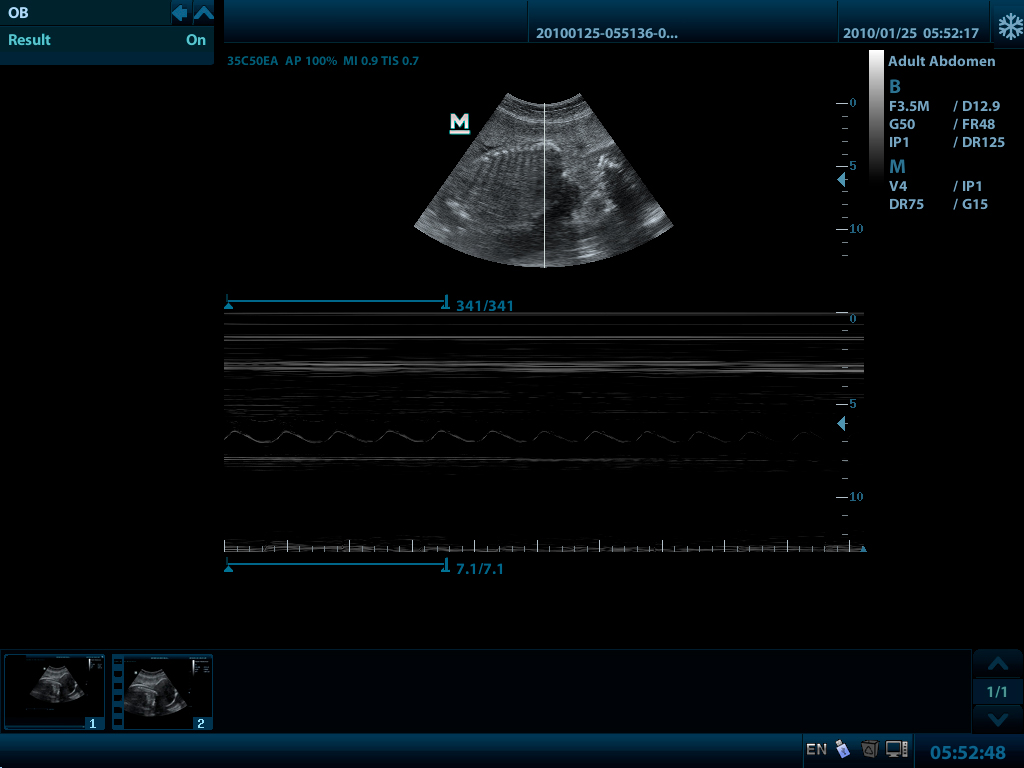

УЗ-сканер DP-50 Color представляет собой новое поколение ультразвуковых систем с цветных доплером компании Mindray. Он оснащен передовыми технологиями визуализации, обеспечивающими более глубокое проникновение и быстрое получение изображений при более высоком разрешении. УЗ-сканер DP-50 color отлично подходит для всех клинических ситуаций благодаря своей новой высокотехнологичной конструкции, повышенной мобильности и удобству эксплуатации.

Формирование мульти-луча Увеличение скорости обработки сигнала от одного луча до 4 раз, что позволяет достигать превосходного разрешения по времени и более высокой частоты кадров.

- PW Импульсно-волновой допплер с автоматической трассировкой спектра

- Режимы сканирования 2D: B/2B/4B/M/B+M